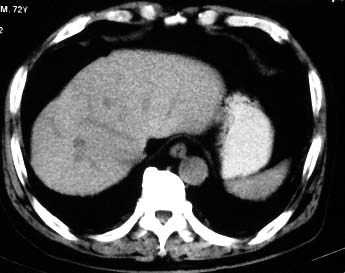

男 56 腹部不舒

典型肝硬化:1、肝各叶大小的比例失常;2、肝表面明显凹凸不整,边缘变钝;3、肝实质密度一般与正常肝无明显改变;4、肝裂增宽;5、门静脉增宽,脾静脉扩张扭曲;6、脾脏虽然不大,但不是所以肝硬化的脾脏都增大。

典型肝硬化:1、肝各叶大小的比例失常;2、肝表面明显凹凸不整,边缘变钝;3、肝实质密度一般与正常肝无明显改变,但肝右叶似可见再生结节影;4、肝裂增宽;5、门静脉增宽,脾静脉扩张扭曲;6、脾脏增大. 脾脏大小的标准有:1脾脏的左右径(大于5个肋单元) 2脾脏的宽度 3脾脏的上下径(超过肝下缘) 请参考.

典型肝硬化:1、肝各叶大小的比例失常;2、肝表面明显凹凸不整,边缘变钝;3、肝实质密度一般与正常肝无明显改变,但肝右叶似可见再生结节影;4、肝裂增宽;5、门静脉增宽,脾静脉扩张扭曲;6、脾脏增大.

典型肝硬化:1、肝各叶大小的比例失常;2、肝表面明显凹凸不整,边缘变钝;3、肝实质密度一般与正常肝无明显改变,但肉眼观察与脾胀密度低或等密度;4、肝裂增宽;5、门静脉增宽,脾静脉扩张扭曲;6、脾脏增大.

肝硬化表现符合,肝脾ct值有倒置,考虑局灶性肝脂肪浸润